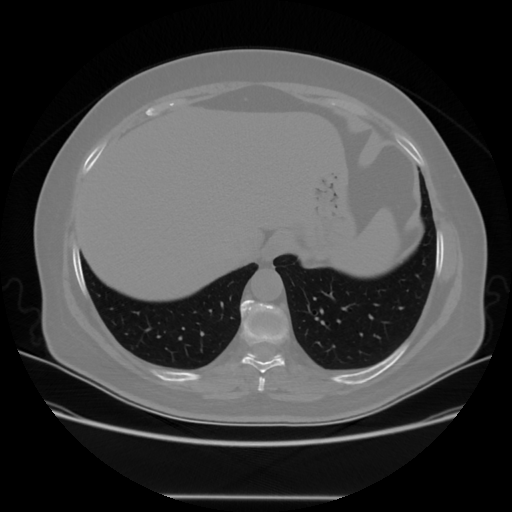

Original NATIVE CT scan (input)

Full window (WL 1023.5, WW 4095 β†’ Low βˆ’1024, High +3071)

Actual HU range: [-1024.0, 918.0]

Lung window (WL -600, WW 1500 β†’ Low βˆ’1350, High +150)

Actual HU range: [-1350.0, 150.0]